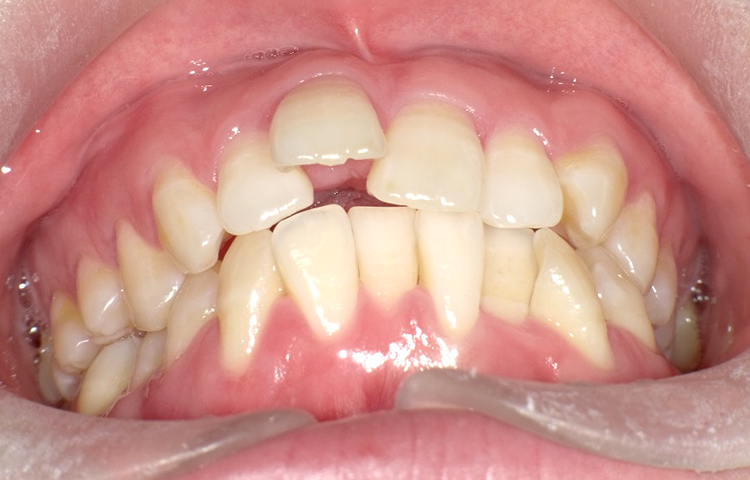

症例5

治療前

治療後

| 主訴 | 右上1番下げたい 1.1間隙間うめたい 上のみ部分矯正希望 |

|---|---|

| 治療 期間 |

約7ヶ月 |

| 治療費 | 175,000円(税込)/調整費用別途 |

| 治療 内容 |

上の前歯部にワイヤーを着けて進めていく、プチ矯正で施術。 |

| 治療の リスク |

奥歯を動かさないので前に出して並べていく。 歯を動かすことで、歯茎が下がるリスクある。 装置による清掃の難しさから、歯肉炎や歯周病、虫歯のリスクが高まる。 矯正終了後は、リテーナーを使用し、後戻りを防ぐ必要がある。 |